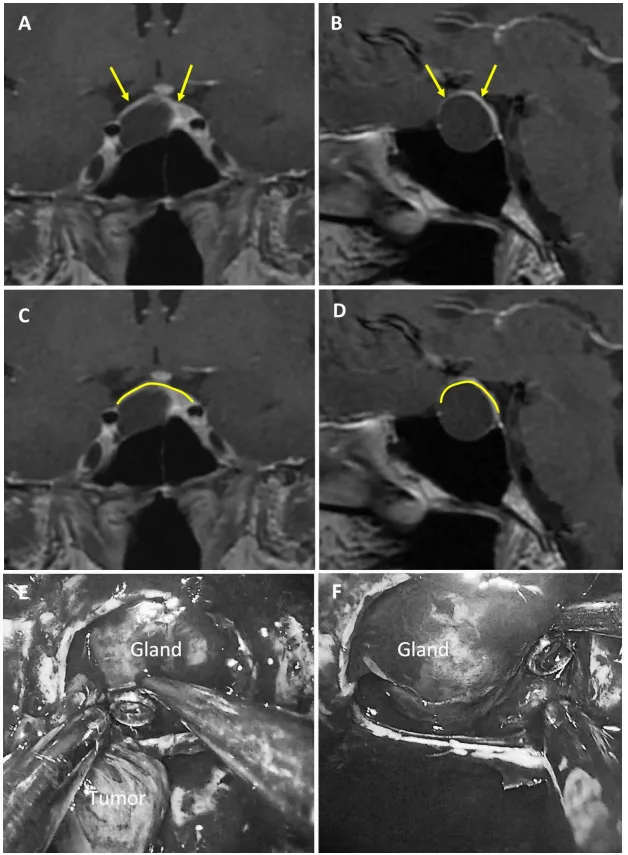

图4:47岁男性生长激素腺瘤患者。a、b术前MRI:黄色箭头指示厚度大于1毫米的强化屏障区。c、d术前MRI:黄色标记线标示强韧屏障位置。e、f术中图像:可见由垂体腺构成的屏障结构。

2混合型鞍隔屏障案例

图5:56岁女性ACTH腺瘤患者。a、b术前MRI:黄色箭头指示厚度大于1毫米的强化屏障区,红色箭头指示厚度小于1毫米的薄弱屏障区。c、d术前MRI:黄色标记线标示强韧屏障区域,红色标记线标示薄弱屏障区域。e术中图像:可见由垂体腺与蛛网膜共同构成的混合屏障结构。